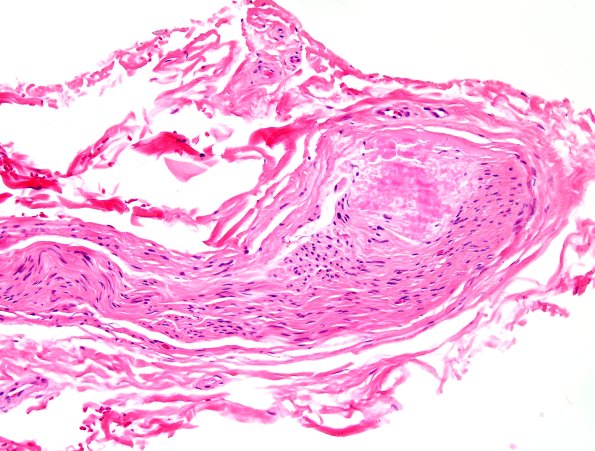

Microscopic examination of routinely stained sections of paraffin-embedded right lower leg nerve biopsy shows focal deposition of eosinophilic amorphous material within the endoneurium and in a rare epineurial blood vessel. (H&E)